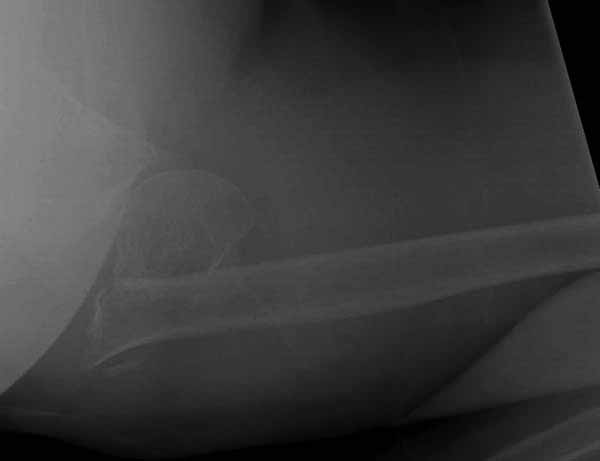

Набор мелких снимков не отражает истинную картину суставной поверхности лопатки, а также качество репозиции головки плеча. Необходимо доказать аксиальным снимком наличие покрытия головки. Правильная маркировка на рентген снимках и соответствие с выставленным диагнозом гарантирует от ошибок со стороной во время операции!

Здесь результат похожего случая, больная 87 лет, отягощенная сердечными делами и два года назад установка pacemaker и нескольких стентов. На третий день, сегодня утром сделали операцию. Послеоперационный псевдовывих связанный с релаксацией мышц и общим обезболиванием.

Имя     : humerus fx injury axial.jpg

Тип     : image/jpg

Размер  : 14321 байтов

Описание: отсутствует

Url     : http://weborto.net:8080/pipermail/ortho/attachments/20110611/5927b955/attachment-0005.jpg